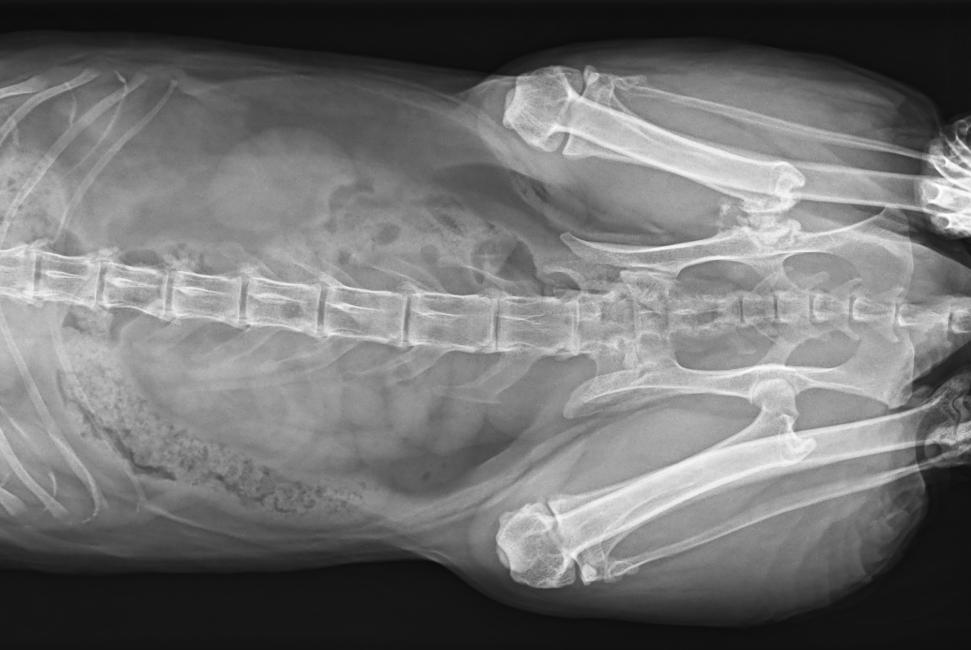

● 17*17大尺寸平板探測器,獲得高質(zhì)量圖像

● 優(yōu)異的空間分辨率及信噪比,提升圖像質(zhì)量

● 采用線噪聲消除技術(shù),使成像質(zhì)量提升40%

● 智能高效的圖像處理軟件,大幅提升圖像質(zhì)量